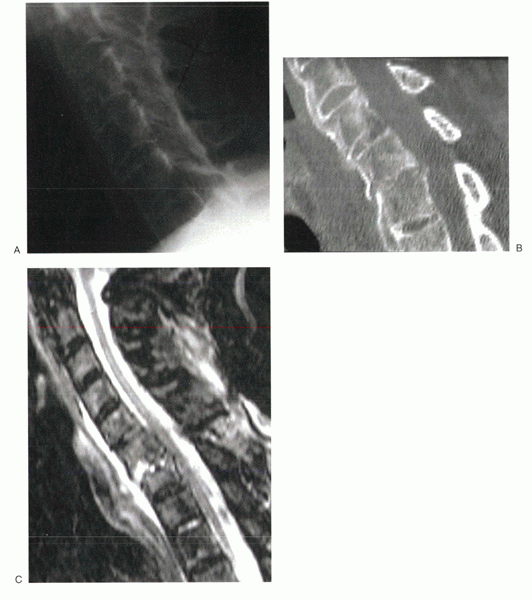

radiographs; on oblique views, they are shown as disruption of the

collar of the “Scotty dog.” On CT and MRI, the defects are seen as

disruption of the posterior arch at the level of the basivertebral vein

(Figs. 2-9 and 2-10).

![]() |

|

Figure 2-9 Sagittal CT reconstructions can be useful in detecting and visualizing spondylolytic defects.

Figure 2-10

On axial CT scans, bilateral spondylolytic defects might be mistaken for arthritic facet joints. This CT slice is at the level of the pedicles, however, which is above (or below) the level of the facet joints. |